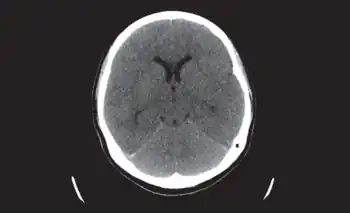

| Generalized cerebral parenchymal swelling, diffuse sulcal space and cisternal space effacement suggestive of meningoencephalitis | |